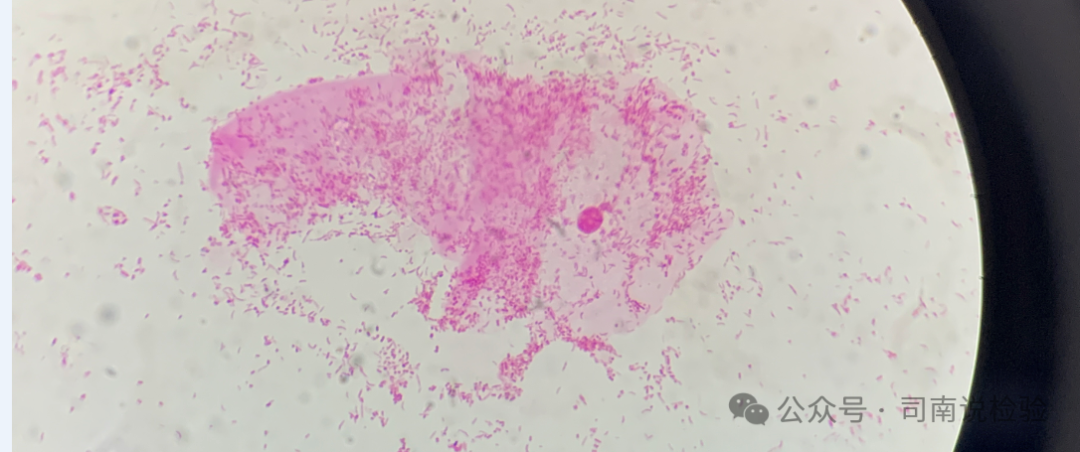

★BV的诊断目前主要根据Amsel临床诊断标准及革兰染色诊断标准。本实验室使用的是Nugent评分诊断标准,Nugent评分4~6 分为BV 中间态,≥7分诊断为BV。

★不是所有的加德纳菌都会产生唾液酸苷酶,也就是说不是所有的加德纳菌感染的患者唾液酸苷酶都会表现出阳性结果,因此在临床实践工作中需要注意干化学要与显微镜检查相配合(或者唾液酸苷酶与脯氨酸氨基肽酶相配合),以显微镜下看到的菌群为主要判断及作为报告回报的依据(细菌性阴道病诊治指南2021修订版的意见上指出,革兰染色Nugent评分标准才是BV诊断的实验室“金标准”)。